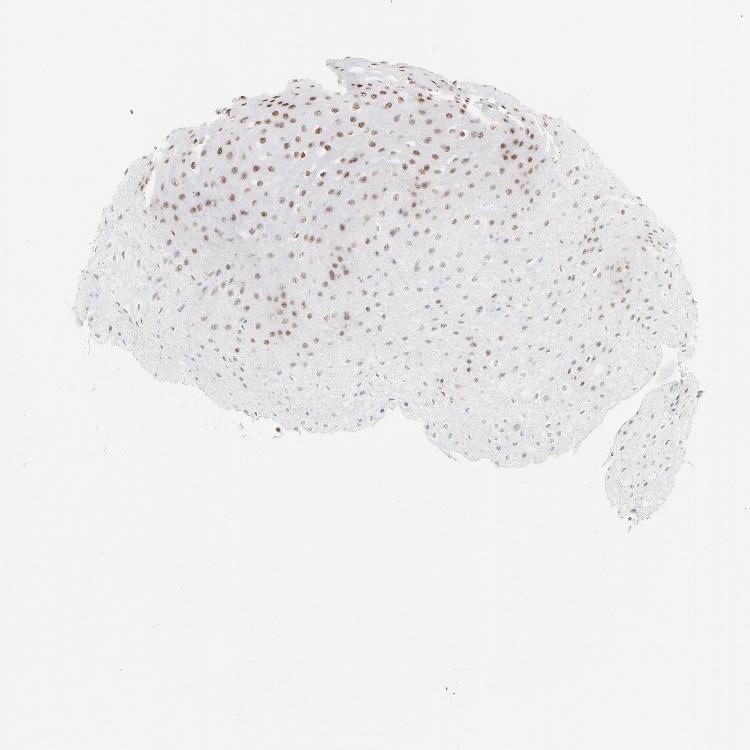

ESOPHAGUS - Antibody stainingi

Antibody staining in the annotated cell types in the current human tissue is reported as not detected, low, medium, or high, based on conventional immunohistochemistry profiling in selected tissues. This score is based on the combination of the staining intensity and fraction of stained cells.

Each image is clickable and will lead to virtual microscopy that enables deeper exploration of all samples and also displays staining intensity scores, fraction scores and subcellular localization as well as patient and tissue information for each sample.

Antibody HPA017284Antibody CAB003703

Squamous epithelial cells MediumHigh